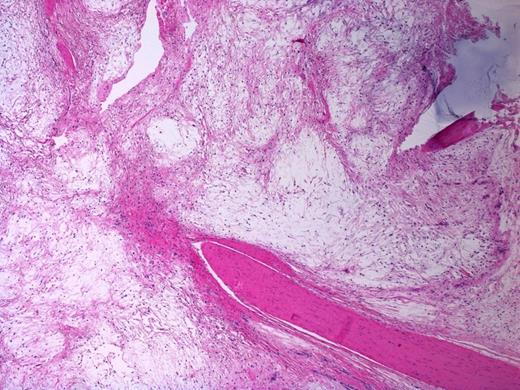

Sections of the lesion showed dense fibrous tissue with nodules of extracellular myxoid material containing scattered histiocytes and stellate to spindled fibroblastic cells. There was no evidence of necrosis, atypia or malignancy; this was consistent with Juxta-articular myxoma. (Figure 4 and 5). At one year follow-up there has been no sign of recurrence.

Bland spindled to stellate fibroblastic cells in a myxoid background. Note the surrounding septa composed of fibrous tissue. H&E stain, 200X magnification